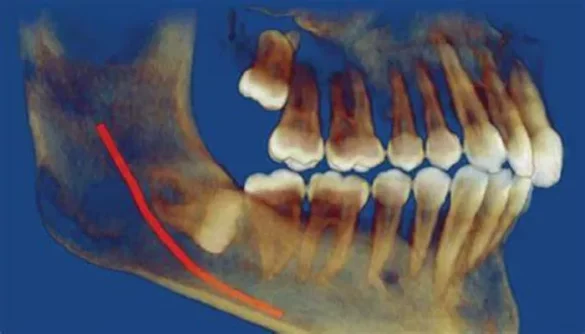

A horizontally impacted wisdom tooth refers to a tooth that is angled in such a way that it grows sideways instead of vertically. This happens when the tooth does not have enough room to break through the gumline properly, causing it to push against the neighboring teeth. It may also be trapped beneath the bone or gum tissue, unable to emerge fully.

Wisdom teeth, also known as third molars, are the last set of teeth at the back of your mouth. These teeth typically emerge in late adolescence or early adulthood, usually between the ages of 17 and 25. While some people experience no issues with their wisdom teeth, many face problems such as impaction. An impacted tooth occurs when there is insufficient space in the jaw for the tooth to emerge properly. When wisdom teeth are horizontally impacted, it means they are growing sideways, usually toward the adjacent teeth. This condition can cause discomfort, pain, and potential dental problems.